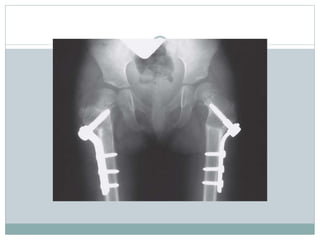

Surgical managment

 The treatment of choice is subtrochanteric osteotomy

make internal fixation easier

 Indications

1. femoral neck-shaft angle less than 90 - 100

degrees

2. Hilgenreiner's-epiphyseal angle greater than 45-

60 degrees

3. documented decrease in the femoral neck-shaft

angle

4. Trendelenburg gait

Congenital coxa vara. Surgical methods of valgus-producing

proximal femoral osteotomies. (A) Pauwels

Y-shaped osteotomy. (B) Langenskiöld

intertrochanteric osteotomy. (C) Borden

subtrochanteric osteotomy.

 The subtrochanteric osteotomy is fixed internally

with either

a) a blade plate or

b) screw and plate combination